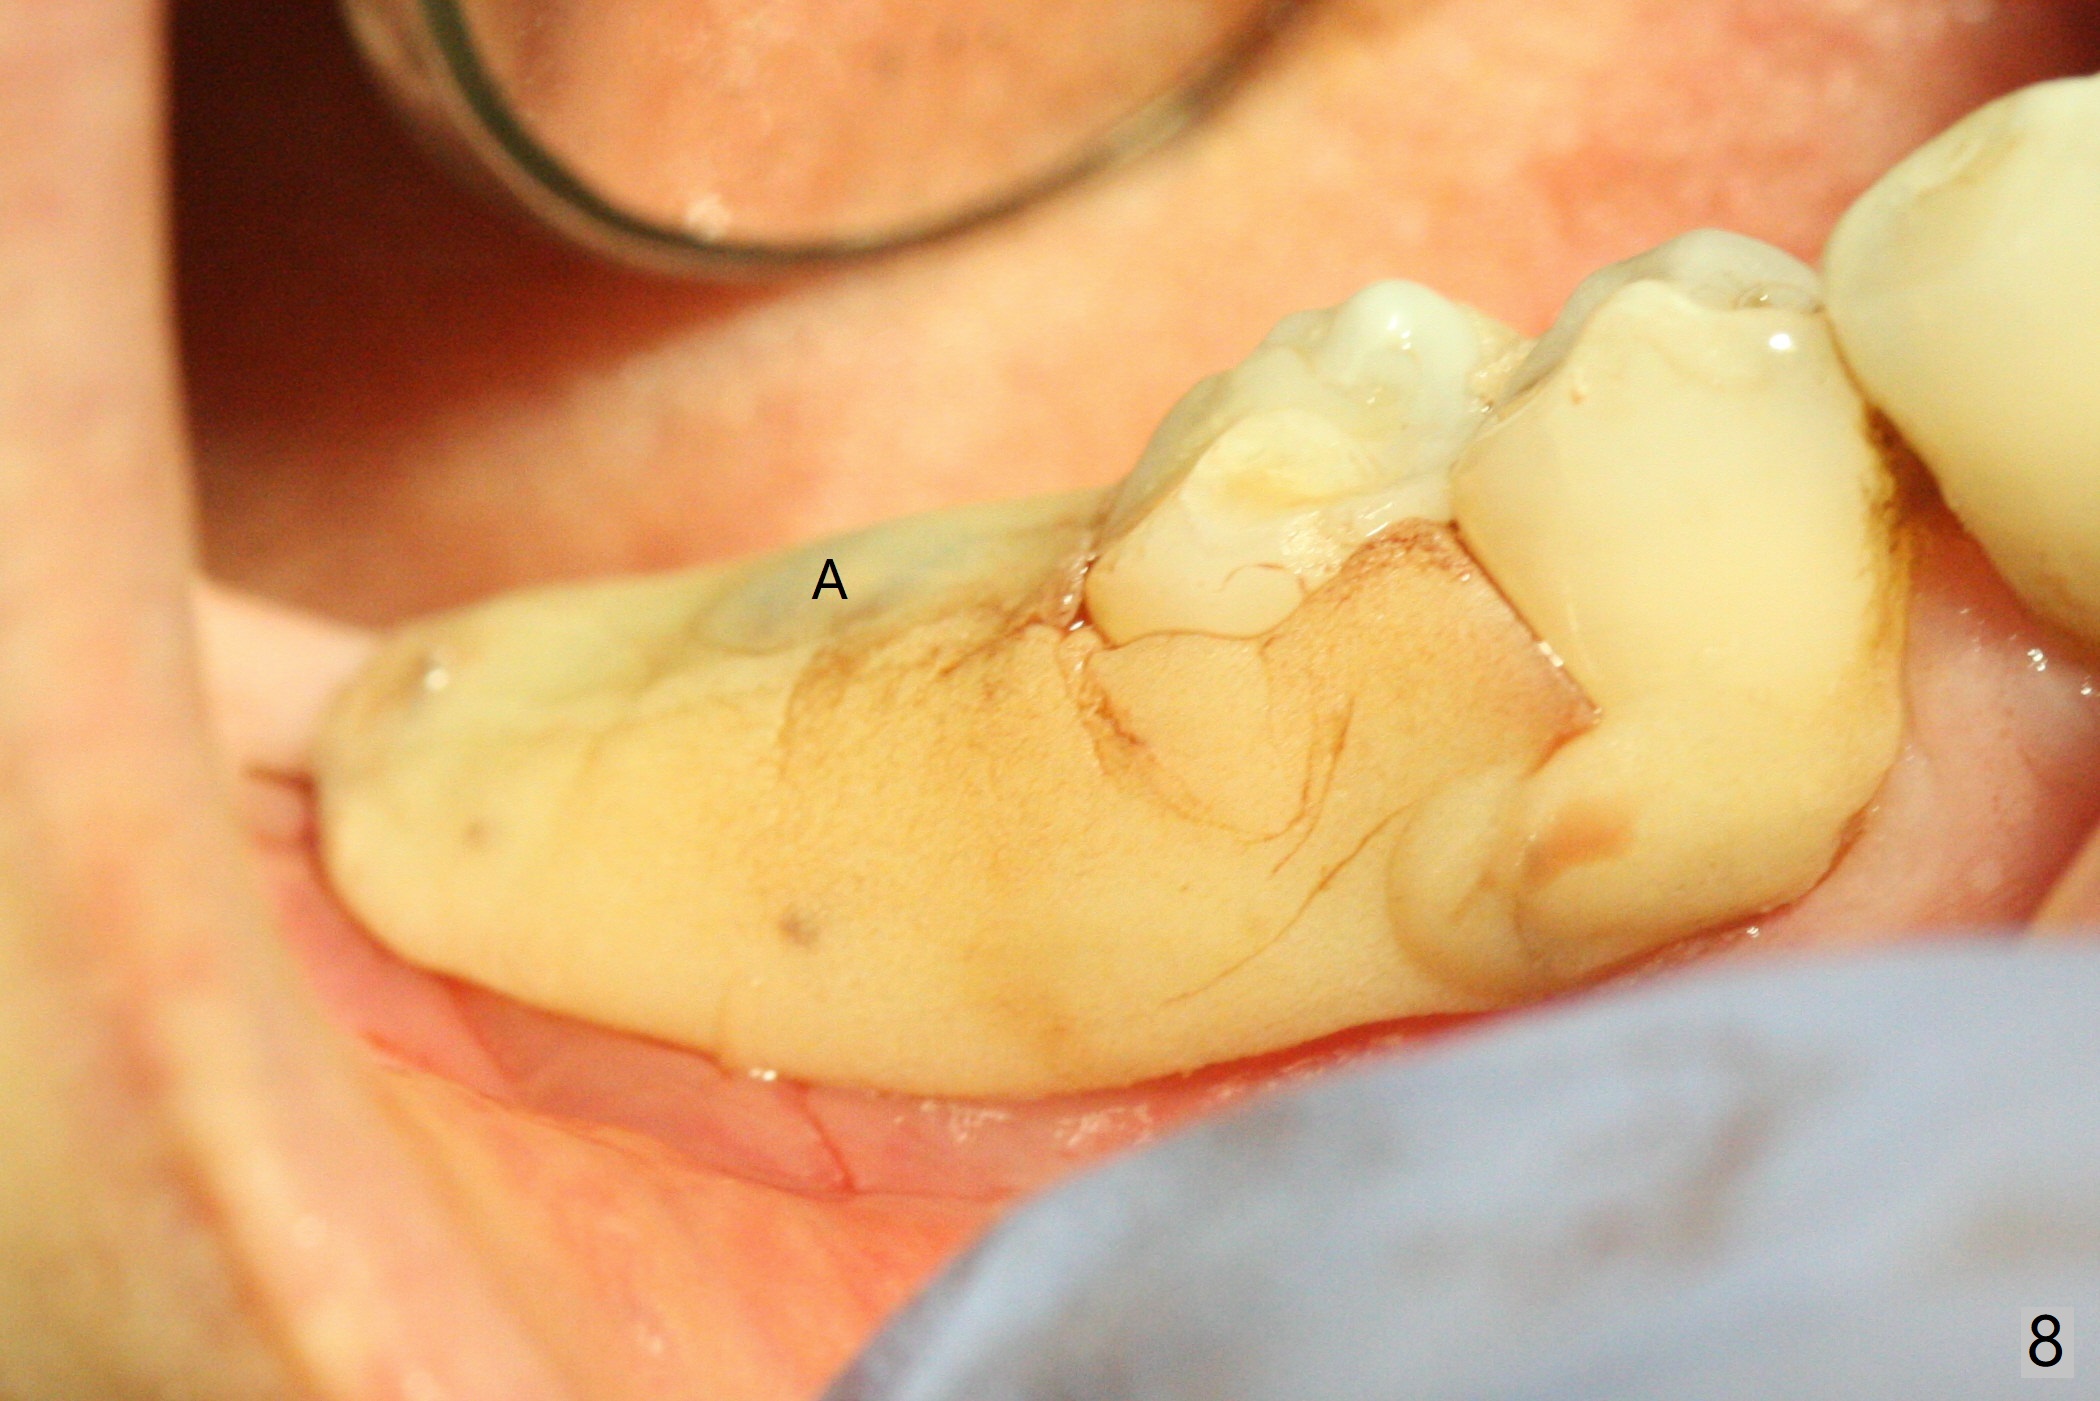

There are signs of periimplantitis at #30 eleven months postop (Fig.1 (* bone loss)). The bony defect (Fig.2) will be filled with allograft mixed PRF liquid to form sticky bone (Fig.3,4), followed by PRF membrane (not shown) and a piece of 6-month membrane (Fig.5). A hole is cut so that the 6-month membrane can slide down the abutment (Fig.2,5 A) to cover the bone graft around the implant (Fig.2,7 I). Setting acrylic is applied around the abutment and neighboring teeth for further protection and holding (Fig.8). The periimplantitis does not resolve nearly 7 months post graft. The implant will be removed. Prepare UF extra wide kit and try to insert 6.5 or 7.0 mm tap. Also prepare sticky bone and Cytoplast for wound closure. Implant removal involves surgical handpiece, 6.2/7 mm trephine bur, elevators, and implant driver. The defect is large (Fig.9) with the low buccal crest (Fig.10) and bone graft with PRF ("sticky bone") is placed, covered by PRF and 6-months membrane (Fig.11). The next implant will be placed with guide. If oral hygiene is not ideal, choose a bone level implant. The middle of the wound dehiscences slightly 8 days postop (Fig.12), accounting for mild loss of bone graft 1 year postop (Fig.14). The keratinized gingiva is apparently wide 1 year postop (Fig.13). There is mild loss of bone graft in the middle of the superficial area (Fig.14). The buccal plate seems to regenerate 1 year postop (pandemic delay, Fig.15).